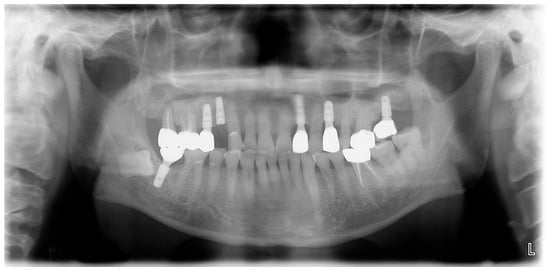

A 69-year-old male patient presenting with severe toothache 10 days before admission and melena 3 days before admission was admitted to the Infectious Disease Department of Kyung Hee University Hospital in the Republic of Korea in March 2025. The patient reported worsening toothache in the right upper gingiva with right facial swelling that began 5 days after a dental implant surgery at the upper right first premolar. Subsequently, the patient underwent incision and drainage at a local dental clinic one day before admission because of periodontitis that had spread to the facial area, as confirmed through the patient’s medical history. The patient had diabetes and was taking hypoglycemic agents. He had undergone coronary artery bypass grafting (CABG) for myocardial infarction 13 years previously. Additionally, he had undergone a prostatectomy for prostate cancer 2 years ago. He had been continuously taking clopidogrel (an antiplatelet agent) since undergoing CABG. The right buccal area of the face was swollen. Dental examination revealed a space abscess around the upper right first premolar (Figure 1). Panoramic dental X-ray showed that the implant fixture was placed in the alveolar bone of the upper right first premolar, and the external part has been removed (Figure 2). The implant fixture at the upper right first premolar was removed and irrigation and drainage were performed at the upper right first premolar and the vestibular area of the upper right second incisor, canine, and first premolar. The initial vital signs were blood pressure, 124/73 mmHg; pulse rate, 87 beats/min; respiratory rate, 20 breaths/min; temperature, 36.5 °C, oxygen saturation level, 98% on room air. Laboratory examination revealed a white blood cell (WBC) count of 6.23 × 109/L (83.0% neutrophils) and a C-reactive protein (CRP) level of 417.0 nmol/L. The aspartate aminotransferase, alanine aminotransferase, and alkaline phosphatase levels were 46, 57, and 97 IU/L, respectively. The serum creatinine level was 1.08 mg/dL and the BUN was 40 mg/dL. The serum sodium level was 129 mEq/L. Plasma level of glycated hemoglobin was 13.5%. Chest computed tomography revealed a mass-like lesion in the left lung with multiple small nodules in both lungs. Two sets of blood cultures were performed on the day of admission using BD Bactec Plus Aerobic/F and BD Bactec Plus Anaerobic/F bottles and a Bactec FX Instrument (Becton Dickinson, Sparks, MD, USA). The patient underwent esophagogastroscopy, which revealed active bleeding from multiple duodenal ulcers and subsequently received hemostatic treatment. A gastrointestinal bleeding dynamic computed tomography (CT) scan showed a liver abscess at S2/3 (3.1 cm) (Figure 3a) with focal septic thromboembolism in the left hepatic vein (Figure 3b). Chest CT revealed mass-like consolidation and air densities in the left upper and lower lobes, along with multiple irregular nodules with ground-glass opacities in both lungs (Figure 3c,d).

Figure 2. Initial panoramic dental X-ray. The implant fixture is placed in the alveolar bone of the upper right first premolar, and the external part has been removed.